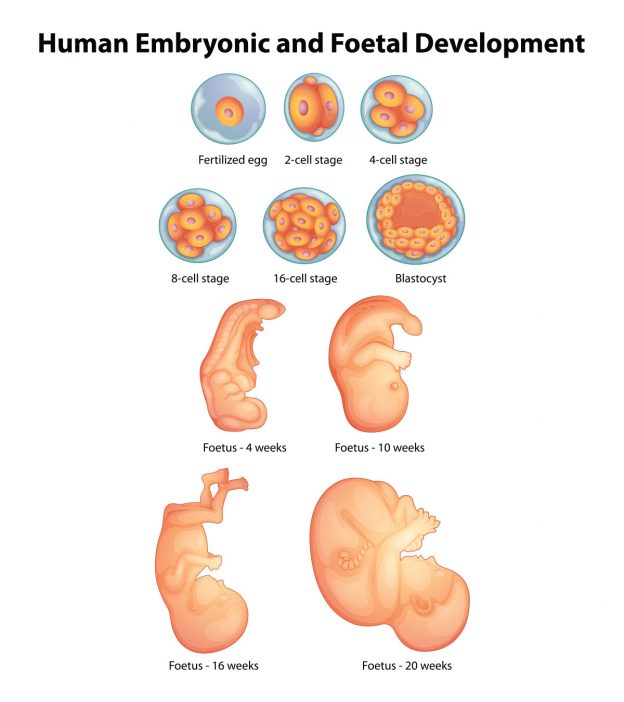

Embryo & Fetal Development – Fetus Illustration Size Comparisons

Prenatal Development | Introduction to Psychology

Fetal Development Week By Week: Stages Of Pregnancy